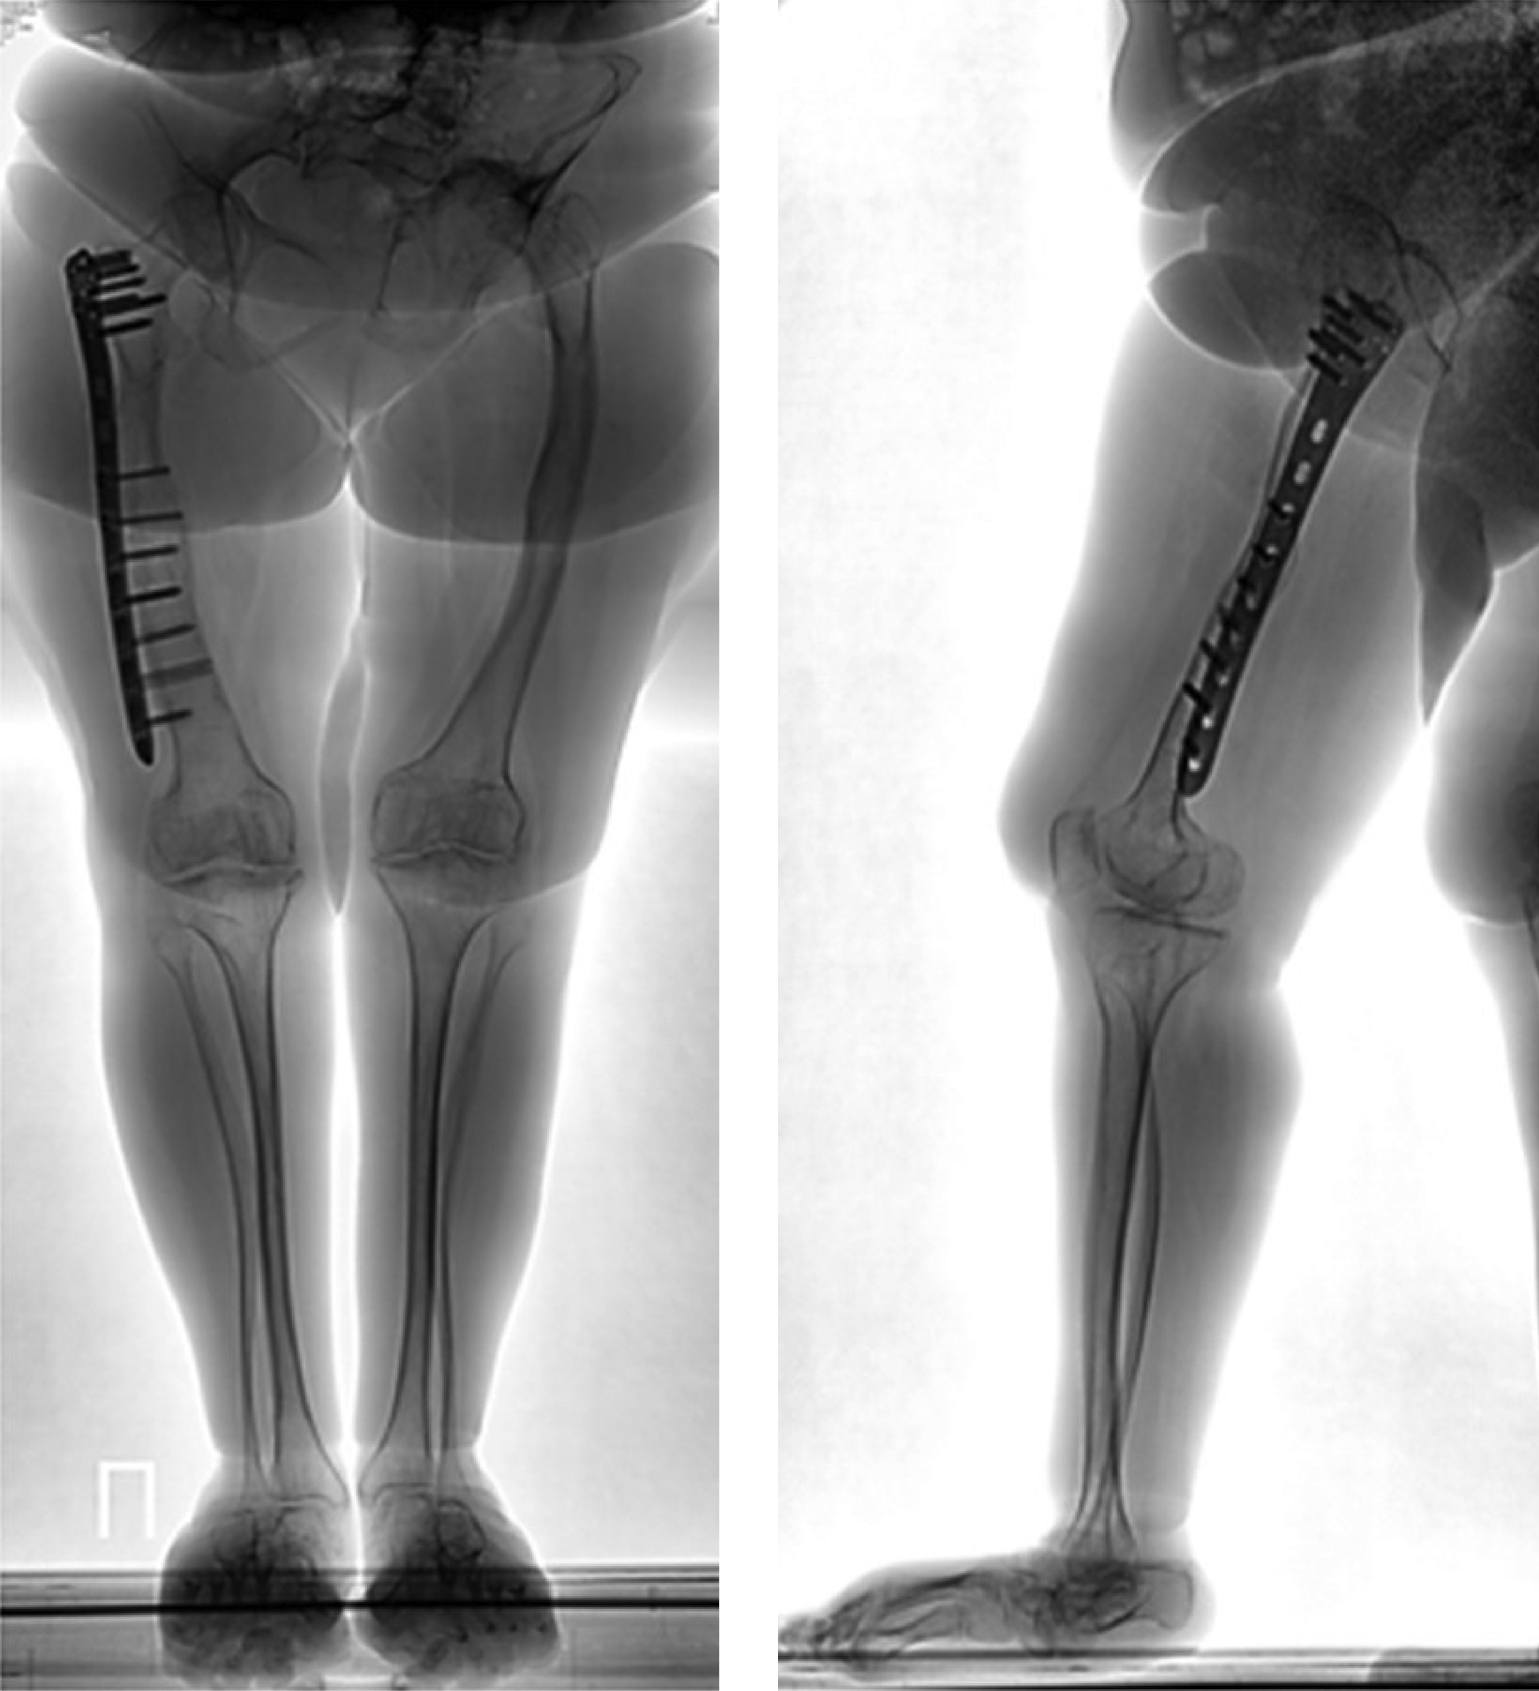

В общей сложности пациентка перенесла 6 переломов: первый — внутриутробный перелом левого бедра, второй в возрасте 10 лет — перелом правого бедра, в 12 лет получила третий перелом — левого бедра (лечение оперативное — резекция ложного сустава левого бедра с коррекцией деформации и остеосинтезом), металлофиксаторы удалены. Четвертый перелом получила в возрасте 24 лет — перелом большеберцовой кости слева, лечилась консервативно. В 29 лет (02.05.2016 г.) получила пятый по счету перелом — закрытый поперечный перелом средней трети диафиза правой бедренной кости, по поводу которого 02.06.2016 г. выполнен компрессионный остеосинтез пластиной с блокированием (рис. 1–2).

Рисунок 1. Рентгенограммы пациентки с переломом правой бедренной кости.

Рисунок 2. Рентгенограммы пациентки после остеосинтеза бедренной кости, блокируемой пластиной.

Во время этого вмешательства были выполнены открытая репозиция отломков с сохранением предсуществующей формы правой бедренной кости и компрессионный остеосинтез пластиной с блокированием. Для деконцентрации напряжения по краям фиксатора в надмыщелковой зоне бедренной кости использован неблокируемый бикортикальный винт 4,5 мм, а в проксимальном отделе блокируемый винт был введен по касательной, кпереди от дуги Адамса. Удаление имплантатов не планировалось. После консолидации кости на этом уровне в сроки 10 месяцев у пациентки восстановилась опороспособность конечности. Однако произошел периимплантный низкоэнергетический подвертельный перелом бедренной кости при падении на правый бок 01.01.2019 г.